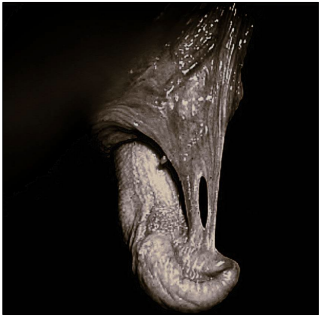

Observe a imagem a seguir:

Enunciado 4509942-1

Qual afecção peniana dos ruminantes está representada na imagem?